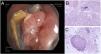

Granulomatous tissue resembling a cancerous lesion completely occluding the LMB was visualized on flexible fiberoptic bronchoscopy. Endoscopic biopsy was performed by cryoprobe (Fig. 1) with both diagnostic and therapeutic intent with decompression. Histopathology revealed the absence of malignant cellularity and numerous actinomyces colonies.

(A) Endoscopic image showing the occupation of the LMB by granulomatous tissue. Around the lesion are the typical yellowish sulfur granules, highly characteristic of the genus Actinomyces. (B and C) Histopathological view by optical microscopy: (B) endobronchial tissue stained with hematoxylin-eosin and sulfur granule indicated by an arrow; (C) this granule can be observed at higher magnifications.